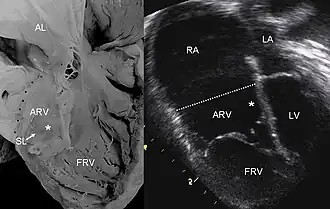

![]() УЗИ изображение патологического состояние сердца при Аномалии Эбштейна. | |

Аномалия Эбштейна — редкий врождённый порок сердца. Данная патология встречается с частотой 1% от всех врождённых пороков развития сердца. Впервые описана в 1866 году патологоанатомом В. Эбштейном. При этом пороке сердца створки правого атриовентрикулярного клапана исходят из стенок правого желудочка, а не из предсердно-желудочкового кольца и неполностью смыкаются (недостаточность трёхстворчатого клапана). Таким образом, полость правого желудочка оказывается уменьшённой по сравнению с нормой, а часть правого желудочка от предсердно-желудочкового кольца (где клапан должен был находиться в норме) до смещённого вниз трехстворчатого клапана становится продолжением правого предсердия. Также при аномалии наблюдается незаращение овального отверстия (между правым и левым предсердиями). Из-за таких анатомических изменений аномалия Эбштейна характеризуется

Эхокардиографическое исследование. Отмечаются деформация эхосигнала от створок и объемное увеличение размеров правого предсердия.